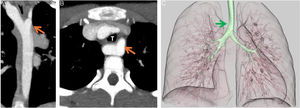

We present the case of a girl aged 9 years with DiGeorge syndrome referred to our hospital due to suspicion of right aortic arch. In the physical examination, the patient exhibited mild dyspnea, cough and occasional choking, with a palpable cervical pulse. The computed tomography (CT) scan of the heart revealed a complex vascular anomaly: a right-sided aortic arch extending cranially to the level of the right thoracic inlet, forming a cervical aortic arch (CAA) (Figs. 1 and 2, Appendix B video 1). The first branch of the aorta was the left common carotid artery, followed by the right subclavian artery, the left common carotid and the left subclavian artery (LSA). The LSA arose from a Kommerell diverticulum (Fig. 3, Appendix B video 2), which, combined with the ligamentum arteriosum, formed a complete vascular right that compressed the trachea (Fig. 3). Cervical aortic arch is an infrequent anomaly in the development of the aorta, occurring in fewer than 1 in 10 000 live births, characterized by an elongated aortic arch extending at or above the medial ends of the clavicles.1 This condition is associated with aneurysms (occurring in up to 20% of cases), coarctation of the aorta, congenital heart defects, Turner syndrome and DiGeorge syndrome.1,2 Given the presence of a complete vascular ring, surgery was the chosen treatment.3